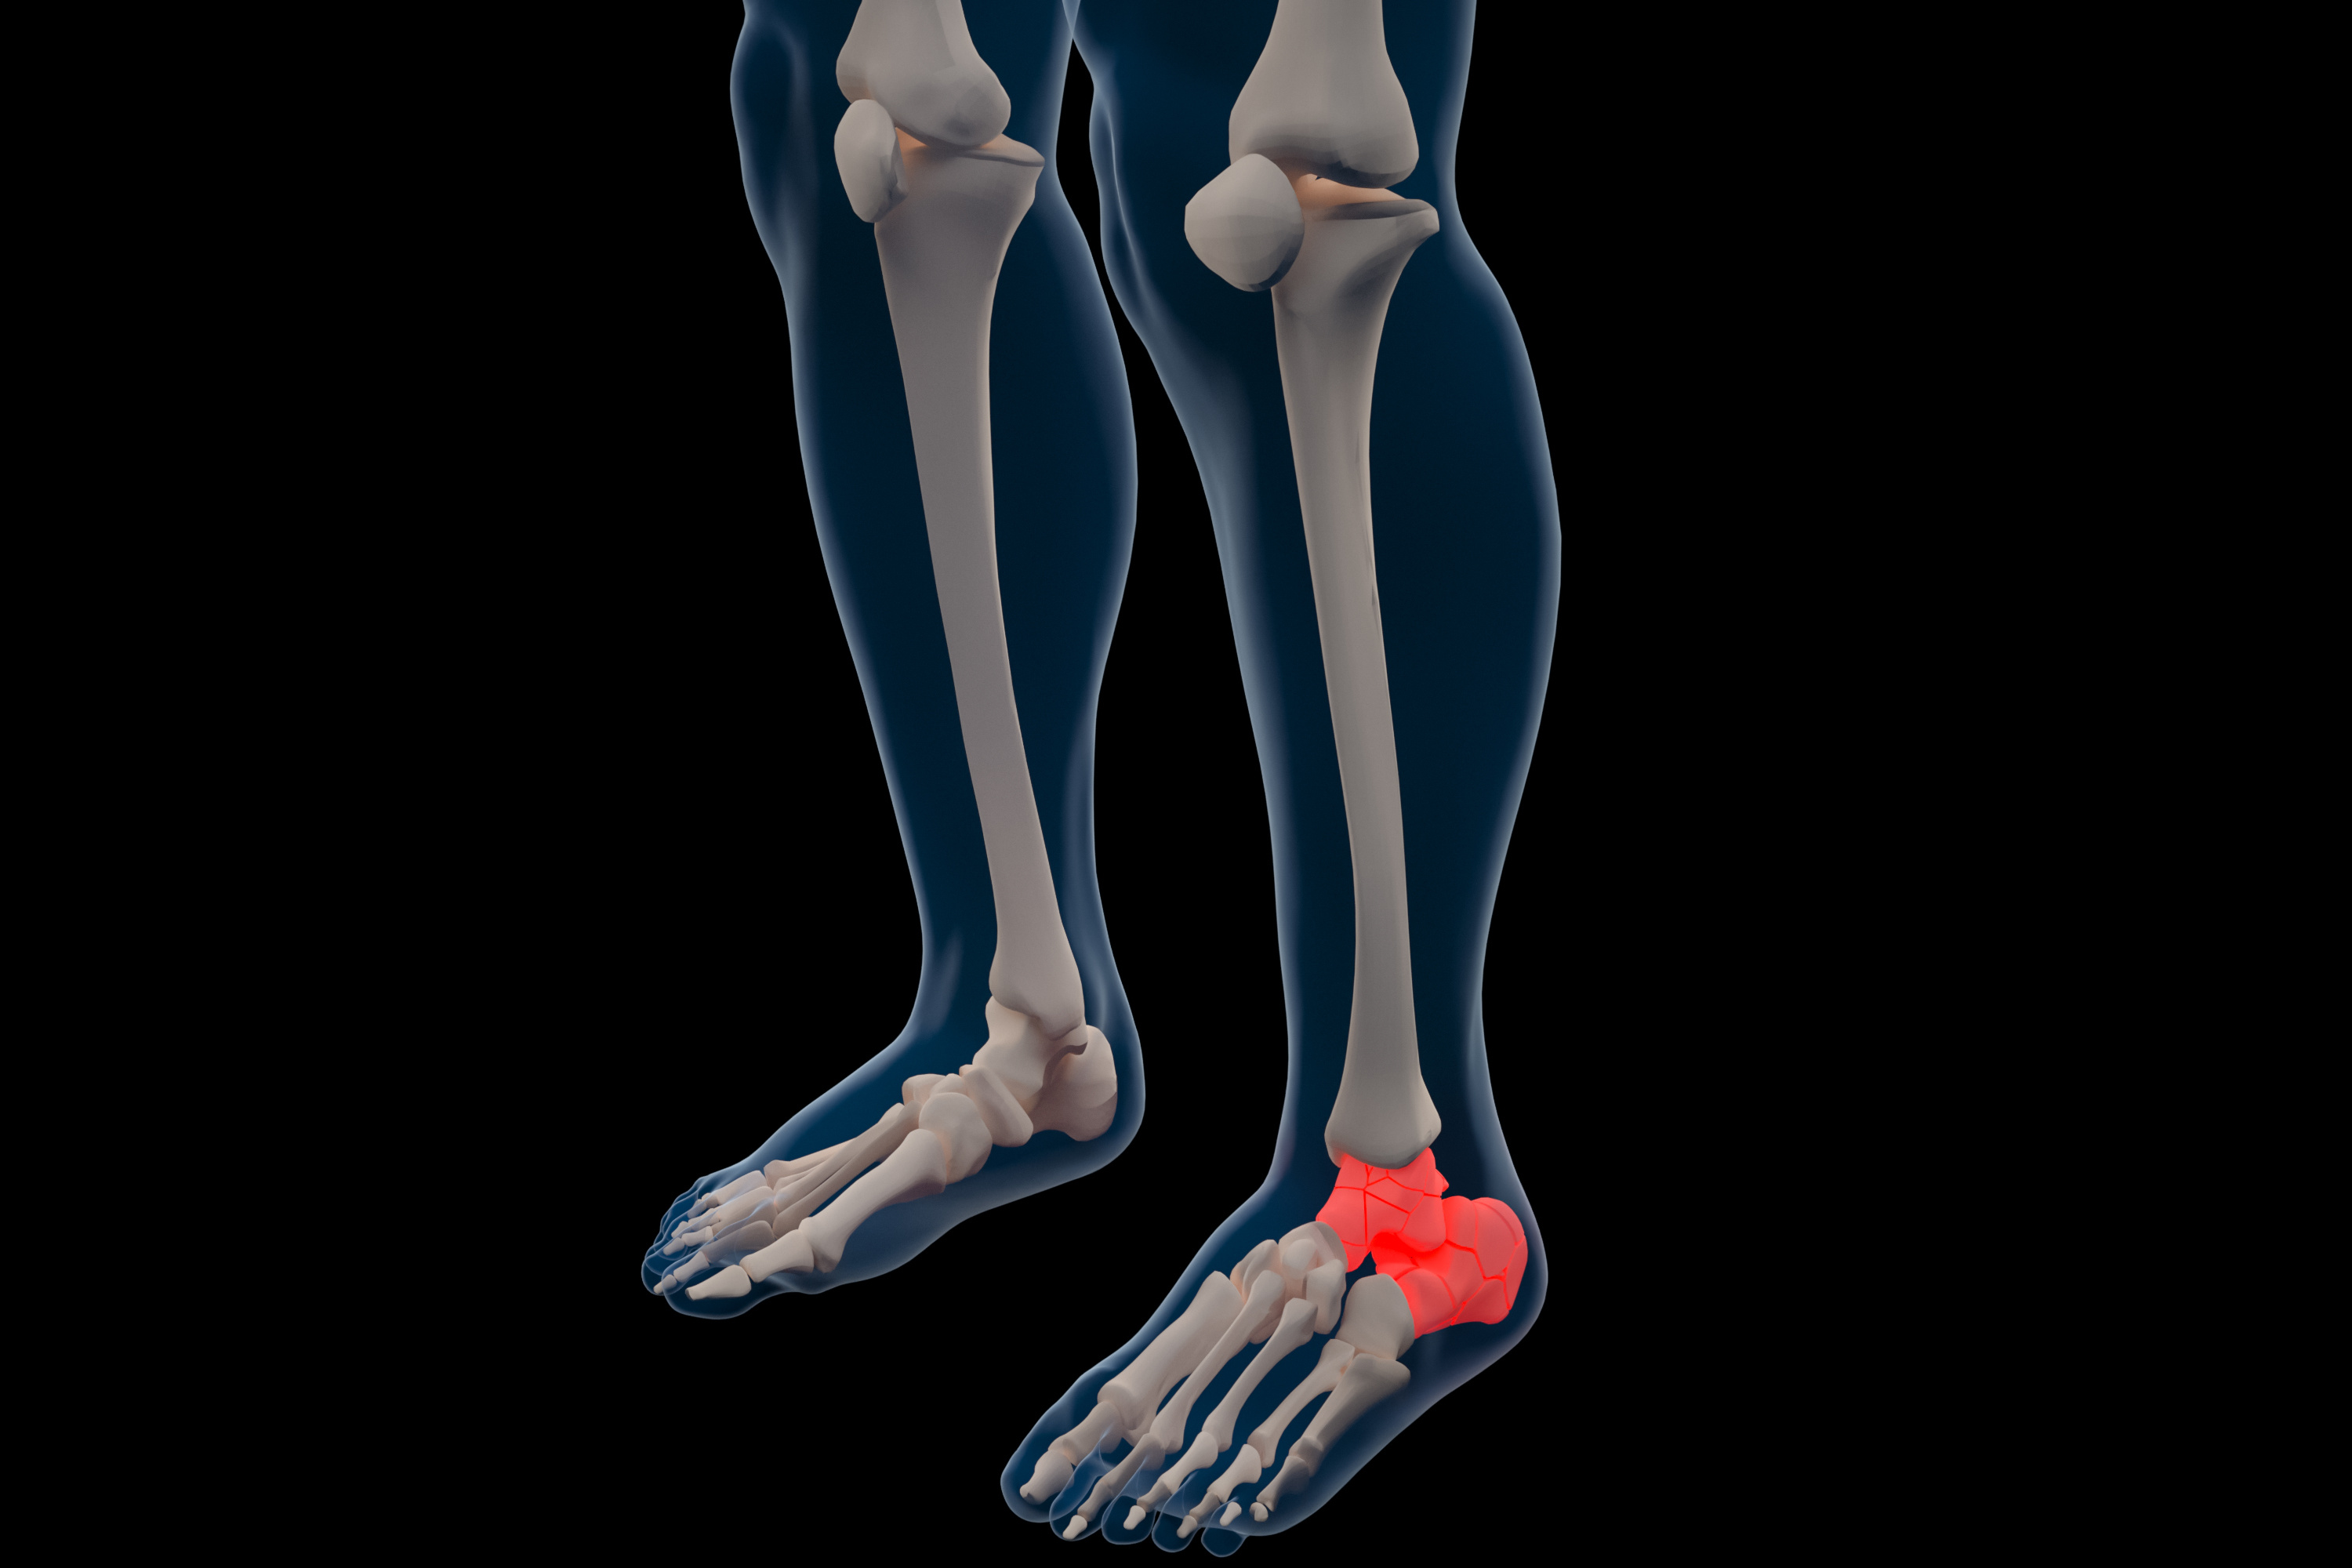

脚里“搭了桥”?聊聊跟距骨桥的诊治!